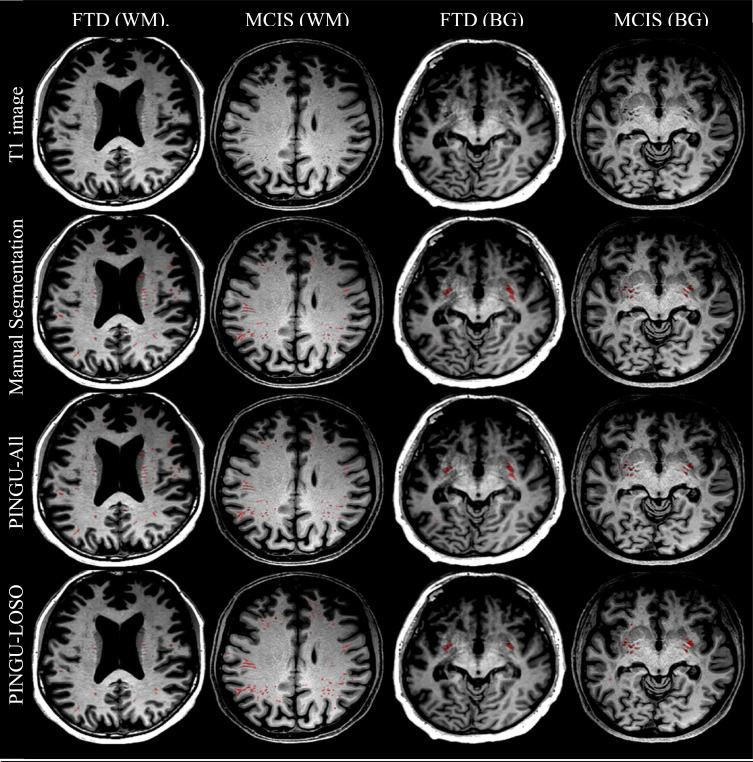

图1.PINGU-All和PINGU-LOSO在T1图像上的叠加,并与"高质量"数据集(MCIS)和"低质量"数据集(FTD)的手动分割进行比较。显示切片是根据手动分割中白质(WM)和基底神经节(BG)中PVS体积最大的切片自动选择的。